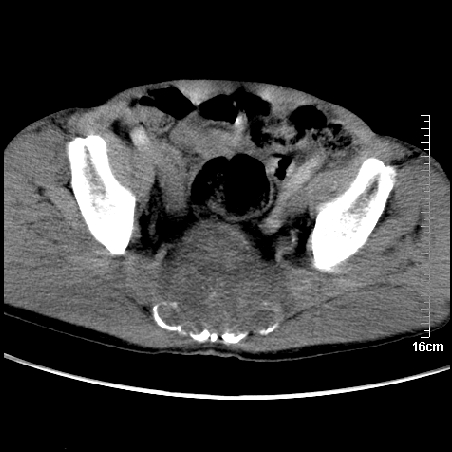

标题: CT16886:骶尾部占位:1.脊索瘤?2.巨细胞瘤? [打印本页]

标题: CT16886:骶尾部占位:1.脊索瘤?2.巨细胞瘤?

增强:

1、骶尾部巨大软组织肿块,部分骶尾骨以被软组织肿块代替,呈不规则侵蚀;病变突向盆腔内;增强扫描病变呈不均质强化;首先考虑脊索瘤。不支持的一点就是病变内无钙化。

2、发生于骶尾椎者须与骨巨细胞瘤鉴别,骨巨细胞瘤一般发在上疗骶椎,肿瘤内无钙化,一般无侵袭性生长的表现。